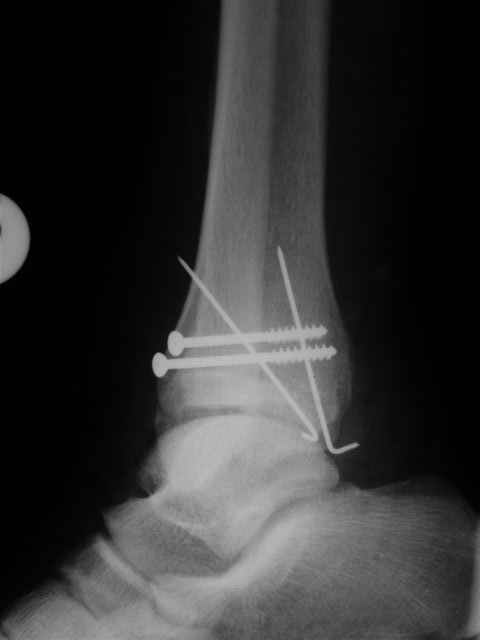

Я предупреждал, что ничего сверхъестественного. Каюсь, что одна из спиц прошла несколько дальше, чем нужно было, но главное - перелом стабилизирован и больной работает суставом в полном объёме, несмотря на представленную раннее травму коленного сустава.

Всего вам Доброго,

Евгений И Чекашкин